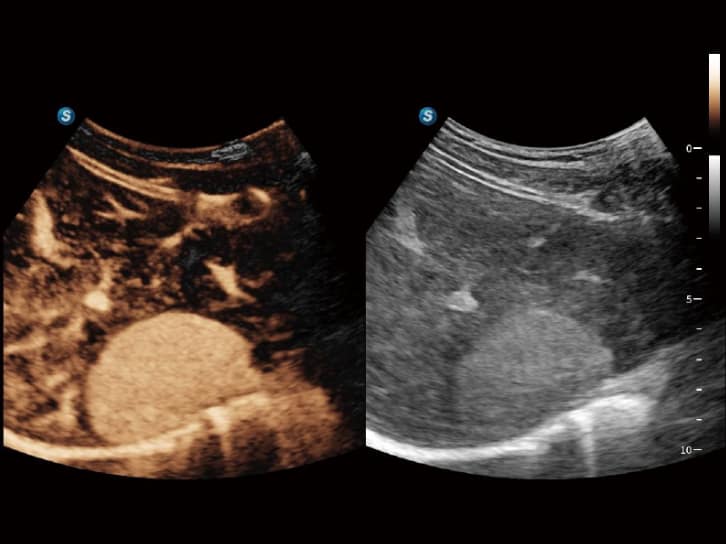

• S-Live Studio: Erzeugt eine brillante, realistische Hautvisualisierung in Echtzeit durch Simulation der Lichtausbreitung.

• AVC Follicle: Automatisiert die Follikelanalyse, sortiert diese nach Größe und markiert sie farblich für eine intuitive Visualisierung.